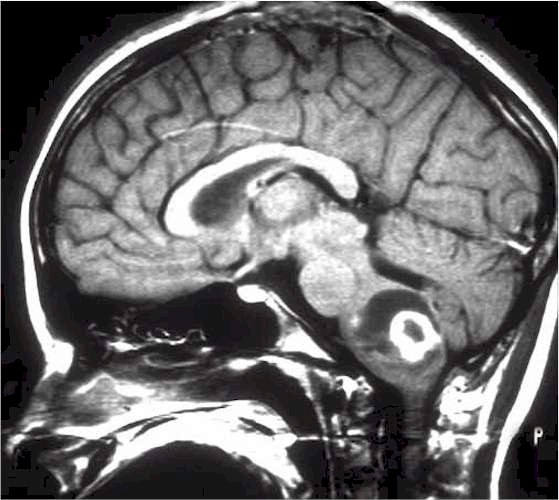

La diagnosi si avvale degli esami neuroradiologici. Per il particolare distretto anatomico da studiare, il tronco, attualmente la Risonanza Magnetica è quella che offre la migliore visualizzazione e definizione delle lesioni tumorali. |

Glioma del

tronco encefalico alla RM. |